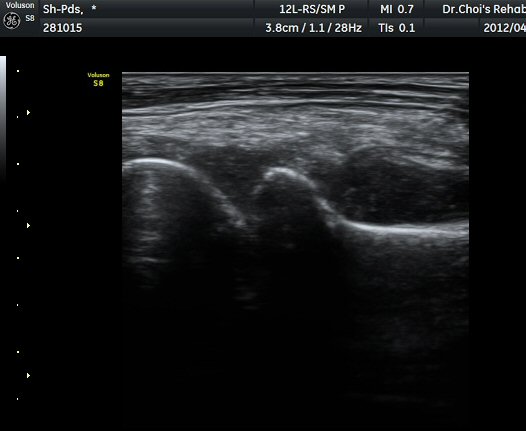

ÃÊÀ½ÆÄ °Ë»ç

ÆÈ²ÞÄ¡°üÀý ¾ÕÀÇ Á¾´Ü¸é°Ë»ç¿Í ÁÖµÎ¿Í Á¾´Ü¸é°Ë»ç¿¡¼­ ½ÉÇÑ °üÀý³» ºÎÁ¾ÀÌ

°üÂûµÊ(»çÁø 1, 2, 3).